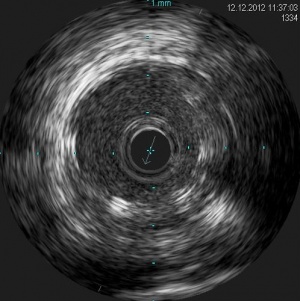

Пациентка Н. 61 года поступила в РКНПК МЗ РФ с клиникой стенокардии III-IV ФК, сохраняющейся на фоне многокомпонентной антиангинальной терапии в условиях ограничения физической активности. При МСКТ коронарных артерий определялись кальцинаты в проекции стенок коронарных артерий: в среднем сегменте ПНА объемом 25 мм³, КИ – 28 ЕД, в проксимальном сегменте ОА объемом 12 мм³, КИ 12 ЕД, во всех сегментах ПКА 21 мм³, КИ -24 ЕД. Суммарный КИ = 64 ЕД. При коронарной ангиографии от 5.12.12 года: сбалансированный тип коронарного кровоснабжения. Ствол левой коронарной артерии не изменен. Передняя нисходящая артерия (ПНА) в проксимальном сегменте с переходом на средний сегмент стенозирована на 71-91% (рис. 6) при компьютерном анализе (QCA), далее имеет гемодинамически незначимые неровности контуров. Огибающая артерия (ОА) имеет неровности контуров в среднем сегменте, артерия тупого края не изменена. Правая коронарная артерия с неровными контурами на всем протяжении, без гемодинамически значимого стенозирования. Во время коронарной ангиографии было проведено измерение фракционного резерва кровотока (ФРК) в ПНА и ОА. ФРК в среднем сегменте ПНА = 0.64, в дистальном сегменте ОА = 0,97. Под местной анестезией раствором лидокаина 2%-10 мл правым радиальным доступом был установлен интродюсер 6F. К устью левой коронарной артерии подведен направляющий катетер PB 3,5 и в дистальный сегмент ПНА проведен интракоронарный проводник. После ряда предилатаций баллонными катетерами 3,0х20 и 3,5х20 мм, было выполнено внутрисосудистое ультразвуковое исследование (ВСУЗИ): в проксимальном и среднем сегменте ПНА определяется гетерогенная эксцентрическая атеросклеротическая бляшка с признаками кальциноза, сужающая просвет на 72,1% площади (рис.7) , протяженностью 37 мм, должный диаметр ПНА в проксимальном и среднем сегменте 3,7 мм. В проксимальном и среднем сегменте ПНА последовательно установлены два биорастворимых сосудистых каркасов Absorb 3,5х28 и 3,5х12мм, давлением до 14 атмосфер, длительностью до 30 сек. Выполнена постдилатация БСК баллонным катетером 3,5х20мм, давлением до 18 атм, длительностью до 30 сек (Рис.8). При контрольном ВСУЗИ в проксимальном и среднем сегменте ПНА определяются БСК полностью расправленные, без признаков пристеночного тромбоза и краевых диссекций. Диаметр просвет артерии в месте установки БСК 3,7 мм (Рис.9). Проводник, катетер и интродюсер удалены выполнен гемостаз места пункции, наложена тугая асептическая повязка. После вмешательства приступы стенокардии не рецидивировали, через 2 дня пациентка была выписана домой в удовлетворительном состоянии.

Рисунок 7. ВСУЗИ ПНА до установки БСК Absorb. Гетерогенная эксцентрическая атеросклеротическая бляшка с признаками кальциноза.